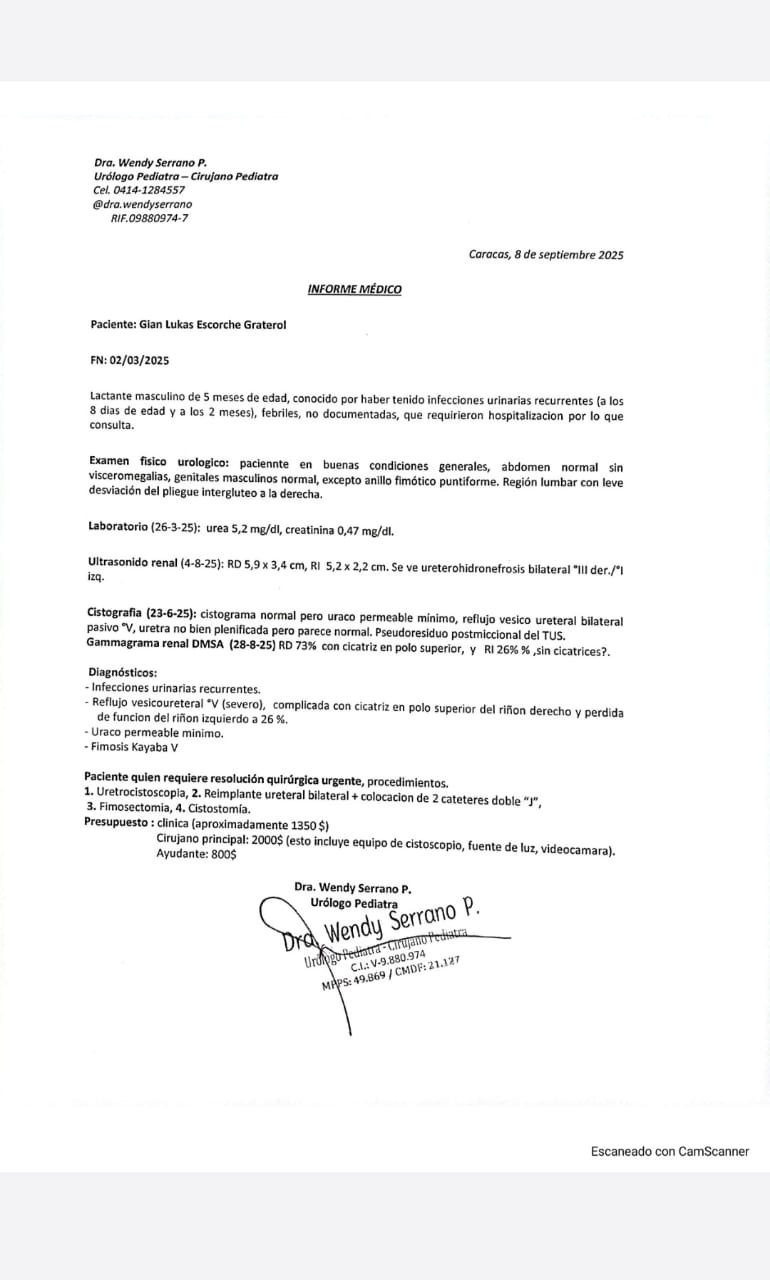

Seguimos en esta lucha y en esta causa hasta lograrlo, poco a poco hemos sumando para que se haga posible todo, gracias a cada personita quea sumado su gran esfuerzo y granito de arena para ir recaudando y poder completar para ser operado, Dios está obrando muy bien en mi vida, así que sigo en pro de ayuda y ahí explico el costo de mi operación, ayúdame compartiendo y difundiendo, ya quiero ser un niño completamente feliz y sano